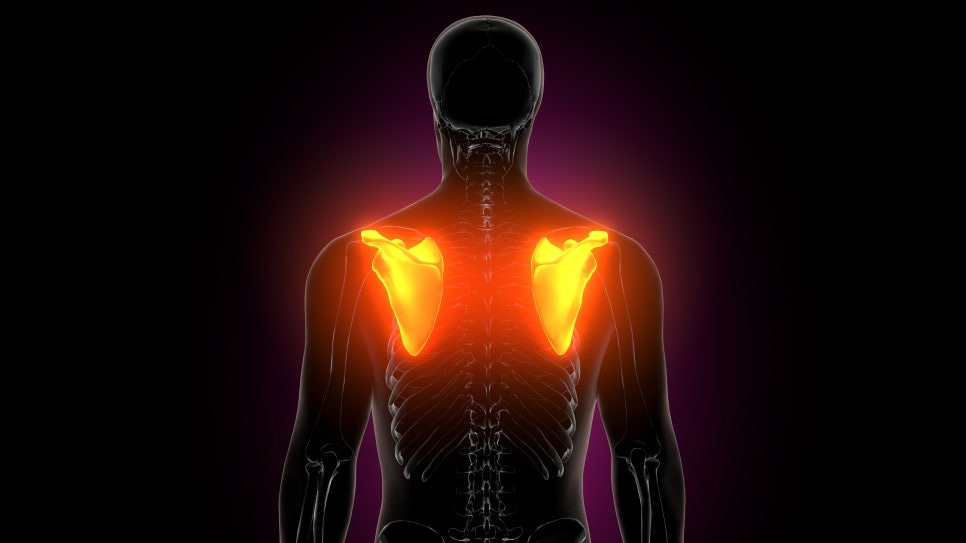

갑자기 양쪽어깨통증이 나타나는 원인은??

어느 날 갑자기 어깨가 욱신거리거나 팔을 들 때 불편함이 느껴진 적 있으신가요? 보통 어깨 통증이라고 하면 한쪽에서 시작되는 경우가 많지만 생각보다 양쪽어깨통증을 동시에 경험하는 분들도 적지 않습니다. 특히 밤에 잠을 자다가 어깨가 쑤셔서 뒤척이거나 옷을 입고 벗는 동작에서 양쪽 어깨가 동시에 불편하게 느껴진다면 가벼운 피로로 넘기기보다는 원인을 조금 더 살펴볼 필요가 있습니다.

양쪽어깨통증, 왜 생길까요?

어깨 관절은 우리 몸에서 가장 움직임이 많은 관절입니다. 팔을 앞뒤로 움직이고 위로 들어 올리고 뒤로 돌리는 동작까지 모두 가능하죠. 이렇게 다양한 움직임이 가능한 이유는 회전근개라고 불리는 여러 힘줄이 어깨 관절을 안정적으로 잡아주기 때문입니다. 회전근개는 크게 네 개의 힘줄로 이루어져 있습니다.